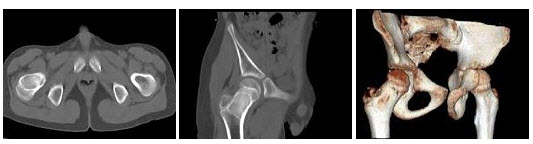

43、多项选择题

男,50岁,涕中带血半年,体检发现右侧颈部多个硬结,CT扫描如图所示,正确的描述或诊断是()

A.右侧筛窦内见软组织块影,边缘不规则

B.软组织影累及对侧筛窦、右侧上颌窦

C.右侧眶内壁、上颌窦壁及颅底骨质破坏

D.右侧筛窦黏液性囊肿